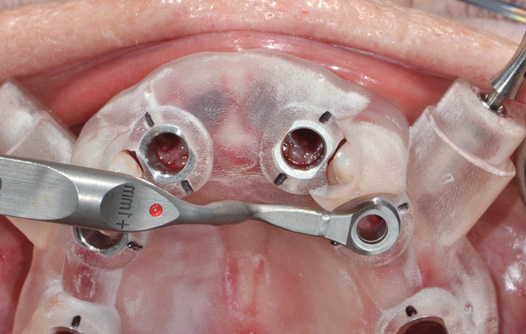

Fig 14. The printed static guide is used to precisely control preparation of osteotomy (Fig 14) and delivery of the implant through the guide (Fig 15).

Figure 14

Fig 15. The printed static guide is used to precisely control preparation of osteotomy (Fig 14) and delivery of the implant through the guide (Fig 15).

Figure 15

Digital Touchpoint 4: Surgical Guide Fabrication (and Transitional Restoration Components)

From the data and collaboration in steps 1 through 3, surgical guides can be fabricated for static surgery, and when indicated, prosthetic components, such as custom healing abutments, provisional crowns, or fixed partial dentures, can be produced for delivery at the time of surgery to guide soft-tissue healing. The static approach, better known as computer-guided surgery, refers to the use of tissue-tooth or soft- and hard-tissue-supported surgical templates. In essence, the virtual implant position planned from the CBCT, IOS, and face-in data sets is reproduced. The guide is produced with master cylinders (portals) through which the osteotomy preparation drills are introduced, and in full-guidance cases, the delivery of the implant is carried out (Figure 14 and Figure 15). Dynamic guided surgery or computer "navigation" traces the virtual implant position directly from CBCT data and employs motion tracking or real-time tracking technology to prepare the implant osteotomy. This makes it possible to determine the actual position of the surgical drill on the reconstructed 3D image provided by the CBCT. The surgeon is guided to the position that was planned preoperatively while he or she performs the surgical procedure. Examples of dynamic navigation systems are Navident (ClaroNav, claronav.com), X-Guide Dynamic 3D Navigation (X-Nav, x-navtech.com), Image Guided Implant (IGI) Dentistry System (Image Navigation, image-navigation.com), Inliant® (Navigate Surgical, navigatesurgical.com), and YOMI®, a robotic haptic guidance system (Neocis, neocis.com).